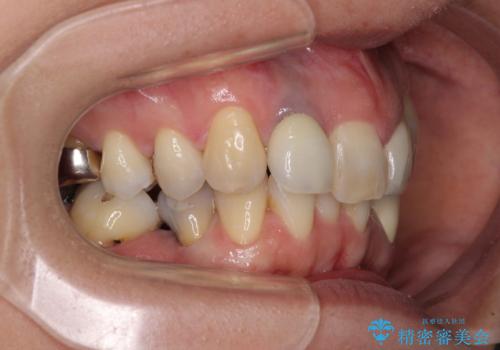

- 非対称な前歯や奥歯の目立つ銀歯を気にして来院された患者様です。

左上前から2番目の歯は、以前裏側に位置していたことから抜歯をされていましたが、前歯の非対称が長年気になっているとのことでした。

矯正治療によって前歯にスペースを作り、左右対称となるようにオールセラミッククラウンにて補綴治療を行うとしました。